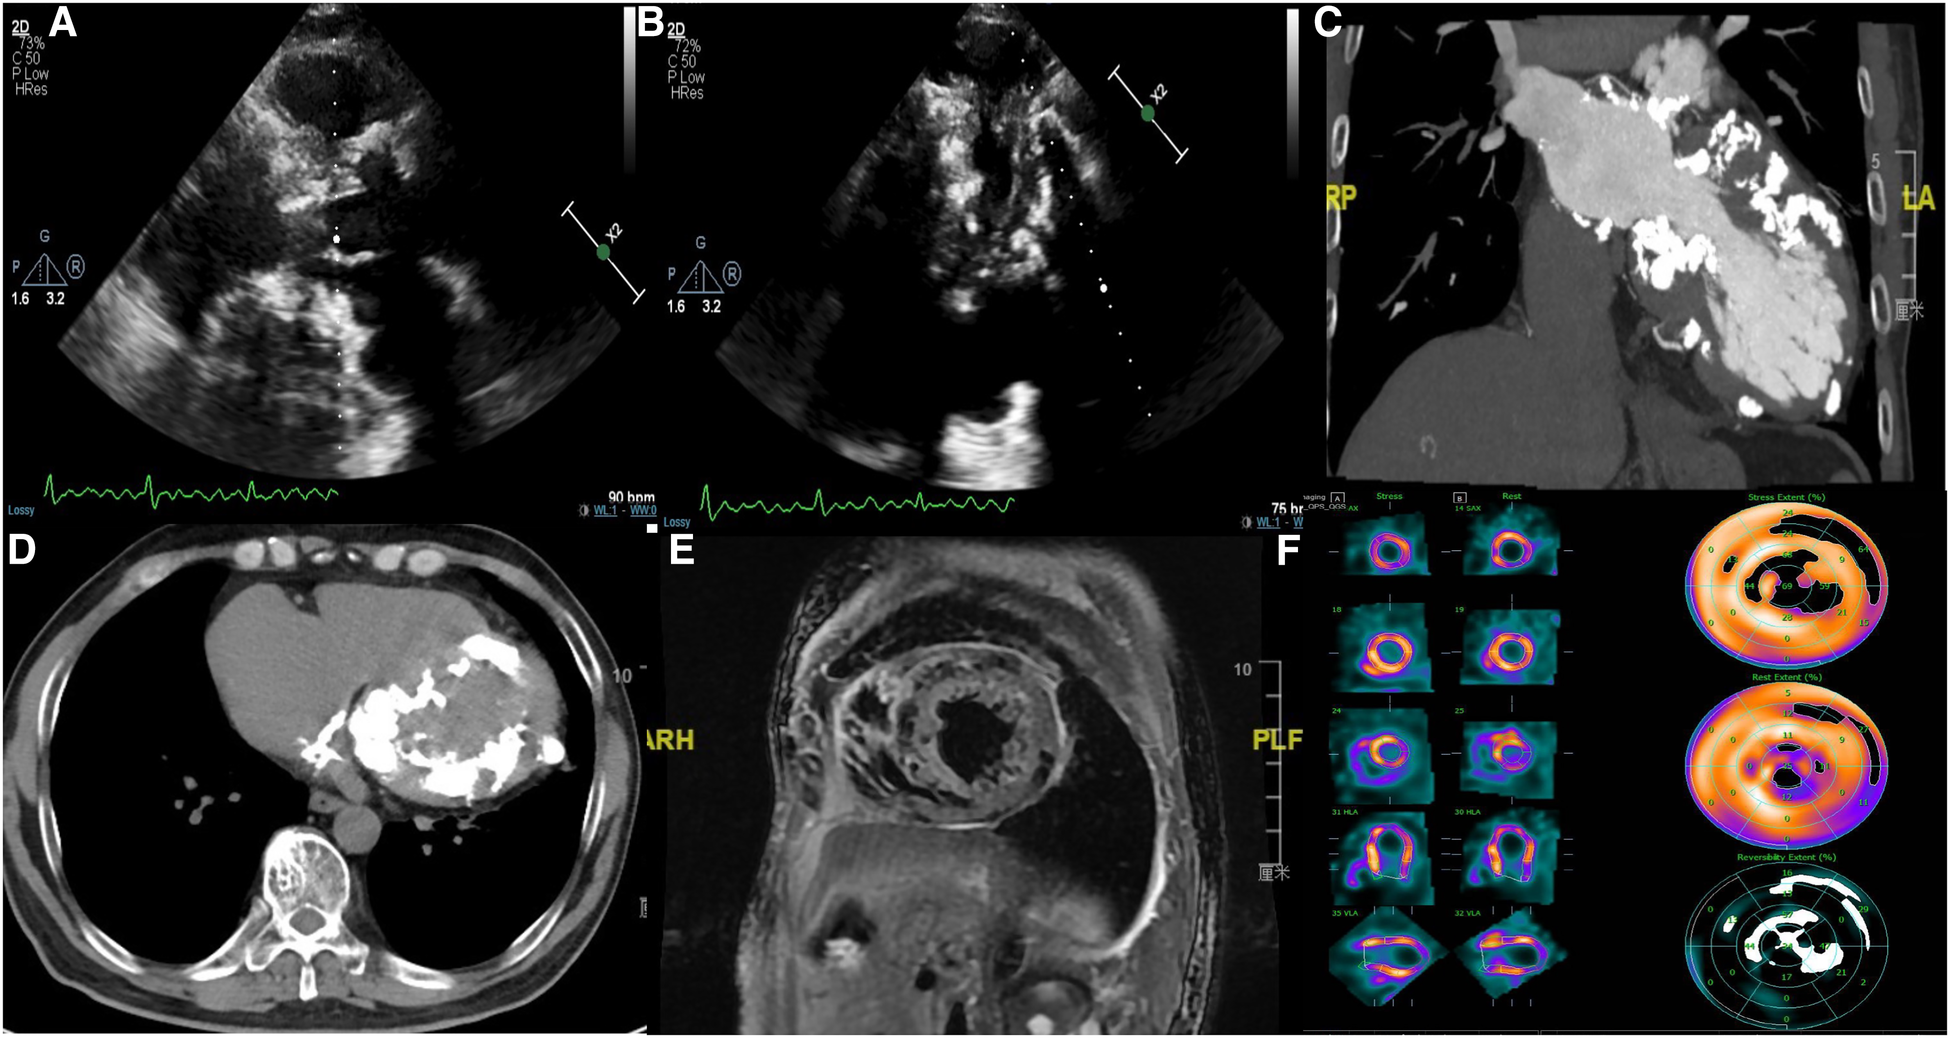

Transthoracic echocardiography showed diffuse myocardial thickening (septal thickness 15.2 mm) and calcification (mainly involving the left atrial wall, left ventricle, atrial septa, mitral annulus, and aortic wall) (Figures 1A, B). Cardiac computed tomography and magnetic resonance imaging also indicated extensive calcifications (Figures 1C–E). Both echocardiography and cardiac magnetic resonance imaging suggested a significant decrease in systolic and diastolic function, but the severe calcification of the myocardium and mitral annulus made the measurement difficult. Radiographic myocardial perfusion imaging (Stress/Rest) showed fixed perfusion defects (Figure 1F). No significant coronary stenosis was detected on coronary computed tomography angiography (Figure 2A). The 3-dimensional reconstruction of the left atrium and pulmonary veins is presented in Figures 2B, C. His laboratory tests showed that N-terminal pro-B-type natriuretic peptide was 2,952 pg/ml (0–125 pg/ml), calcium was 2.32 mmol/L (2.11–2.52 mmol/L), and phosphorus was 0.7 mmol/L (0.85–1.51 mmol/L). The patient had no other relevant abnormalities in hematology or biochemistry, including renal and liver function, thyroid function, calcium metabolism, autoimmune function, and inflammatory indicators. He has no history of previous myocardial infarction or tuberculosis. Therefore, we speculated that myocardial calcification may have developed secondary to myocarditis. However, detailed information on the previous history of myocarditis was missing.

Figure 1

(A,B) Transthoracic echocardiography showing interventricular septal hypertrophy, extensive calcification in the left atrial wall, left ventricle, mitral annulus, and aortic wall; (C,D) cardiac computed tomography showing extensive calcification in the left ventricle, left atrium, atrial septa, and mitral annulus; (E) cardiac magnetic resonance imaging showing diffuse myocardial calcification; (F) radionuclide myocardial perfusion imaging (stress/rest) showing fixed perfusion defects.